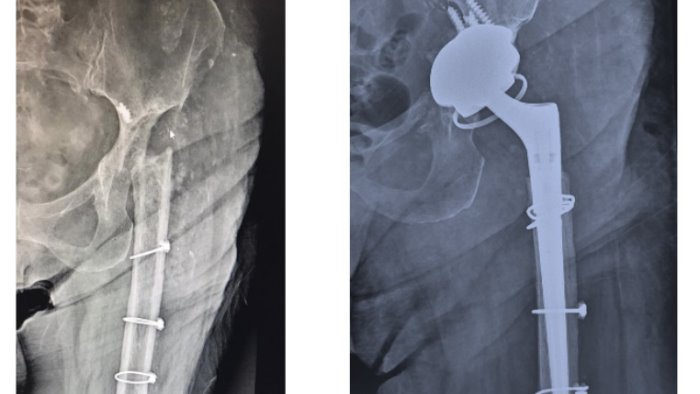

Un eccezionale intervento chirurgico di revisione protesica dell’anca è stato eseguito presso la Divisione di Ortopedia e Traumatologia dell’Ospedale Sacro Cuore di Gesù – Fatebenefratelli di Benevento, diretta dal dottore Salvatore D’Auria. Si tratta di una paziente napoletana di 78 anni, già sottoposta per 14 volte ad interventi chirurgici di protesizzazione dell’anca sinistra, revisioni multiple ed, infine, asportazione completa dell’anca presso nosocomi regionali ed extraregionali.

L’equipe operatoria composta dai chirurghi Antonio Piscopo, Salvatore D’Auria, Marco Molfini e Stefano Cacciapuoti, ha sottoposto la paziente ad un delicato intervento di chirurgia ricostruttiva dell’anca: la neoarticolazione è stata ricostruita con osso di banca ed un impianto protesico da revisione.

L’intervento chirurgico, durato circa due ore, è perfettamente riuscito e la paziente notevolmente commossa, ha ripreso una deambulazione autonoma. In gergo chirurgico si tratta di un cosiddetto “case report internazionale” per numero di interventi precedenti, per la particolare complessità della ricostruzione anatomica della neoarticolazione e per l’inevitabile grande carica emotiva della paziente e della stessa equipe operatoria.